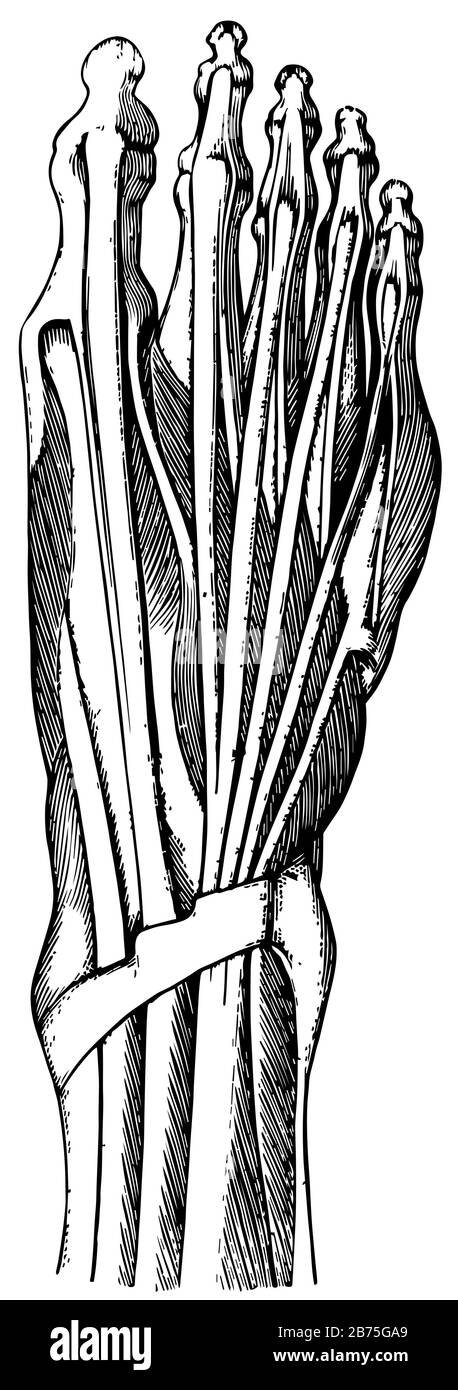

RF2BTGWJJ–Schéma d'un pied humain, l'un est la vue de côté et l'autre a de la semelle, dessin de ligne vintage ou illustration de gravure.

RF2BTGDWM–Les os de la Tarsal du pied sont situés dans le milieu du pied et les zones de l'arrière du pied humain, dessin de ligne vintage ou illustration de gravure.

RF2B74PR1–Le pied est construit sous la forme d'une demi-dôme ou d'une demi-voûte, d'un dessin vintage ou d'une gravure.